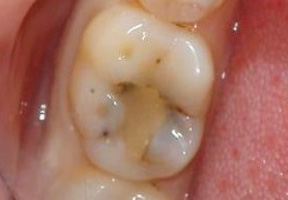

Le foto seguenti mostrano un esempio di carie nascoste in un dente sotto un ripieno: